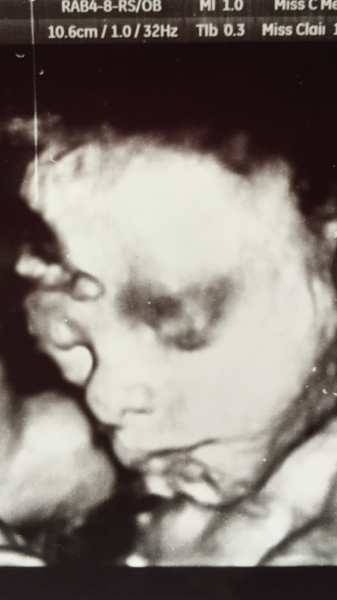

Amazing pic rufus!

Not eaten any chocolate today, nearly killed me, not sure how I'm going to survive the building site crap without chocolate. I've put on 3 kgs in 4 weeks. So a total of 18kgs! Think I'm winning the most weight gain trophy!!! Maybe cutting out sugar is a good idea, my arse is the same size as my bump but at least I am balanced. Baby is measuring completely normal for dates. Got another 3D pic today, best yet, although he does look like he has a black eye.

Amazing pic rufus - what a cutie. Not good about the no chocolate though, I'm a chocolate fiend at the moment Confused

Fab photo rufus Smile

rufus what a cutie!!

Oh wow rufus that pic is amazing!! So detailed!